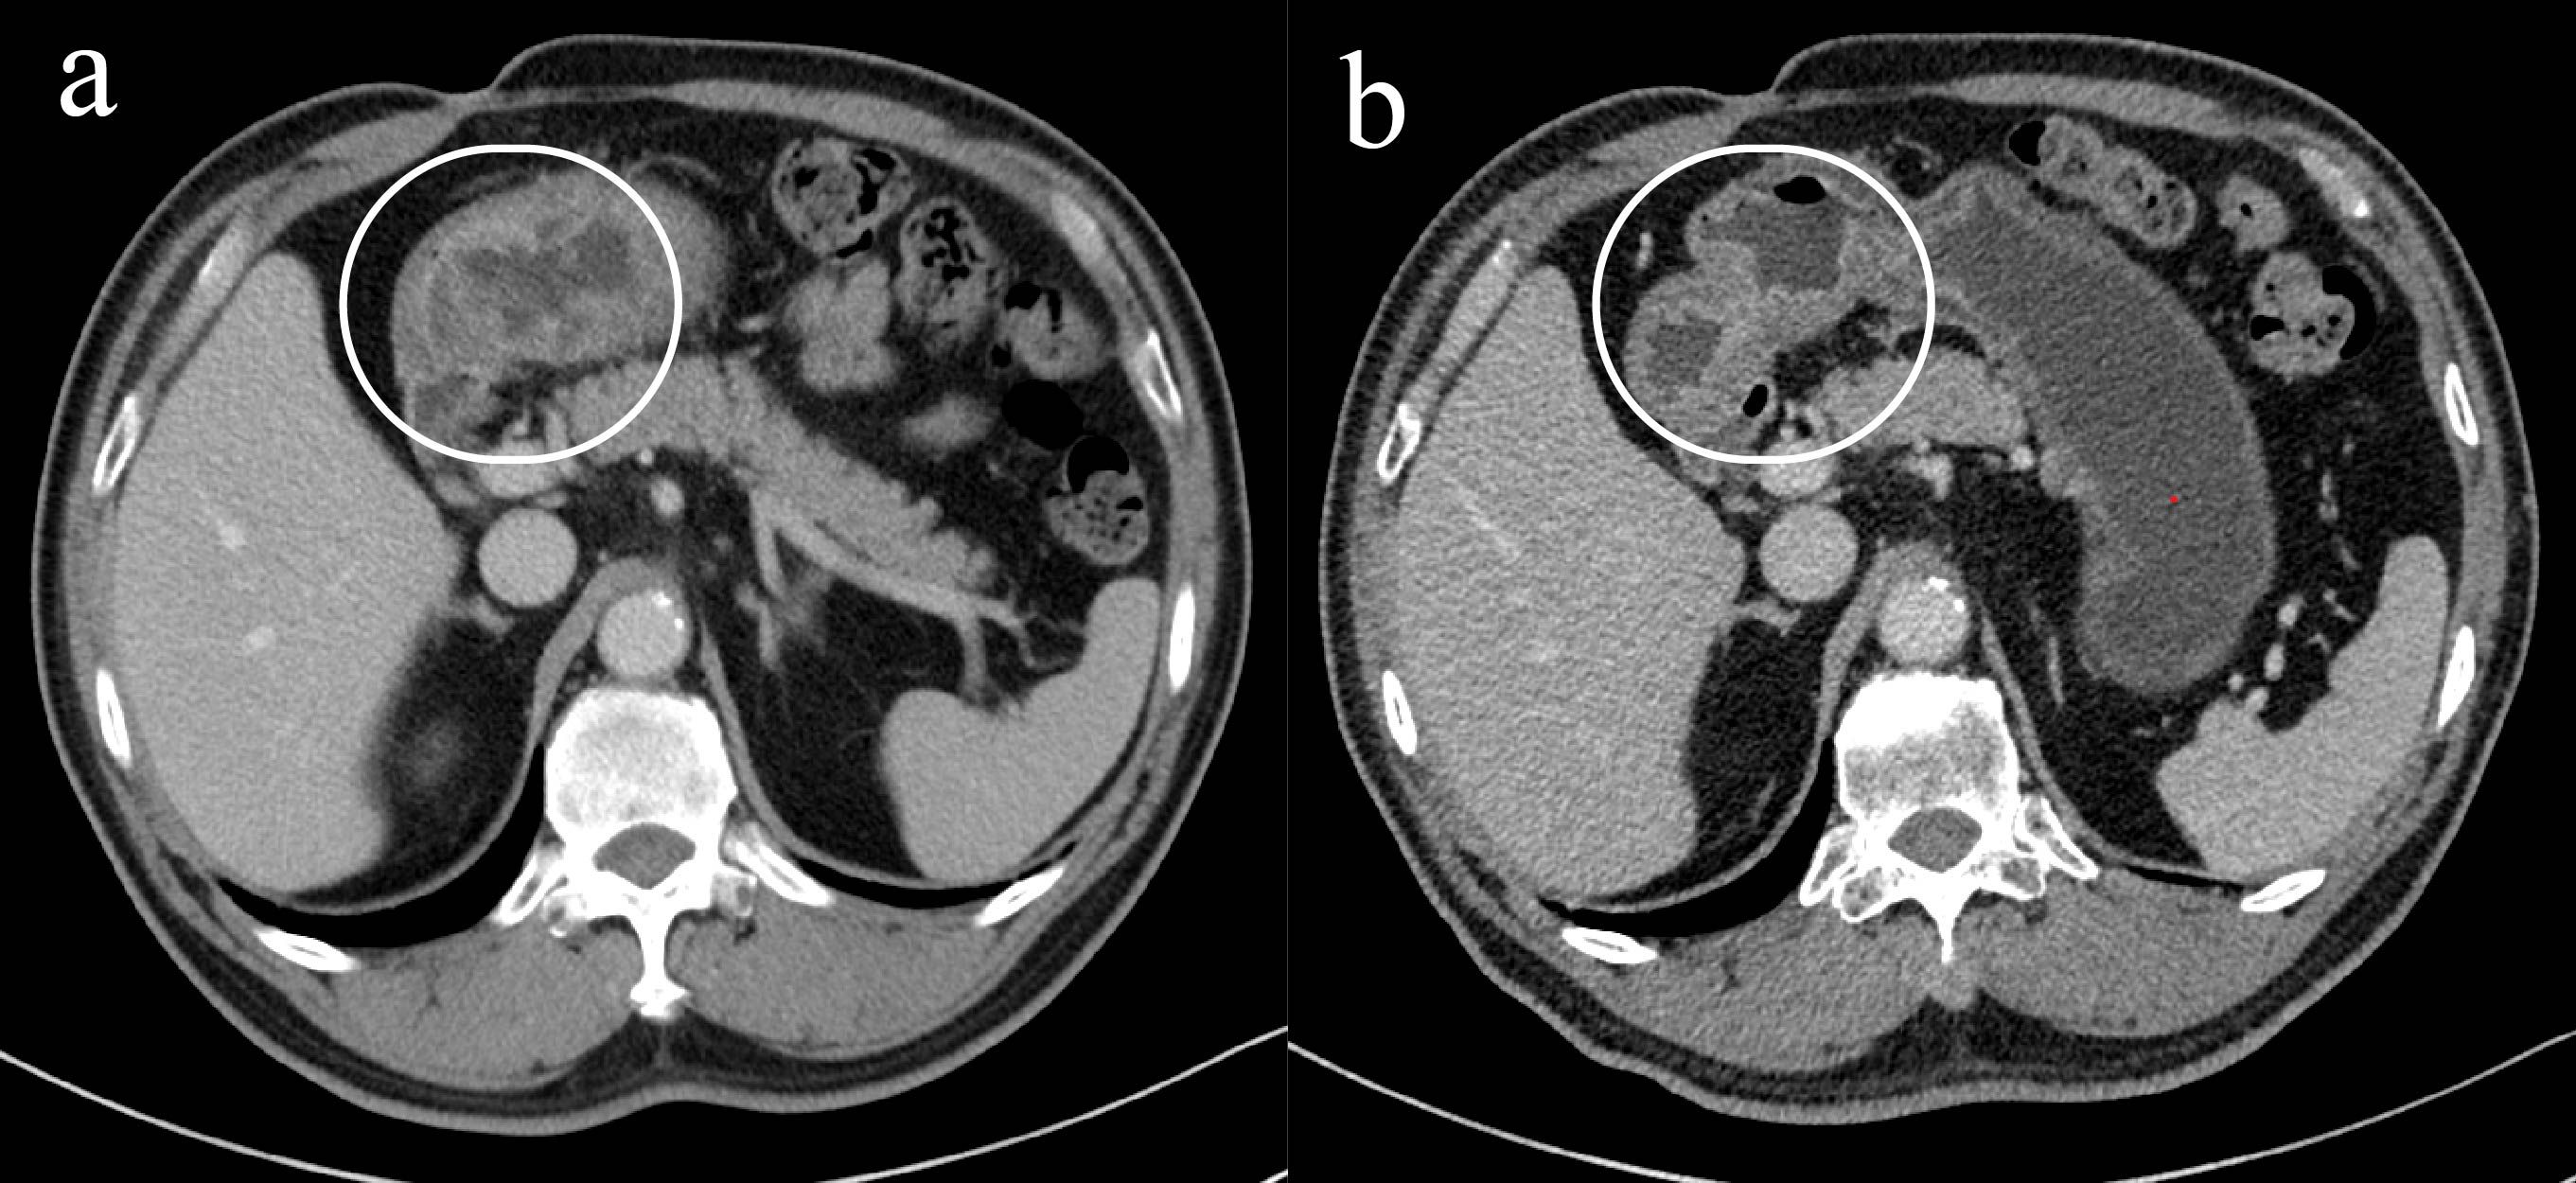

Gastric and colorectal cancers present significant therapeutic challenges, particularly in the elderly population, who often have comorbidities and diminished tolerance to standard treatments. This report describes an 85-year-old male with concurrent stage III gastric adenocarcinoma and stage IIIb microsatellite stable colorectal cancer, who declined both surgery and chemotherapy. Subsequently, the patient was treated with an innovative regimen consisting of endoscopic intratumoral injections of Oncolytic adenovirus H101 in combination with the PD-1 inhibitor tislelizumab. Following this combined therapeutic approach, the patient demonstrated notable tumor shrinkage and downstaging, accompanied by a reduction in serum tumor markers, including CEA and CA19-9. Additionally, there was an observed increase in CD8⁺ and CD4⁺ T-cell counts, indicating systemic immune activation. The treatment was well-tolerated, with the only reported adverse event being mild fever. The patient achieved nearly 4 months of progression-free survival and a substantial improvement in quality of life. This case highlights the potential of combining oncolytic virotherapy with PD-1 inhibition as a promising and novel personalized strategy for treating elderly patients with advanced gastrointestinal cancers who are unsuitable candidates for conventional therapies.